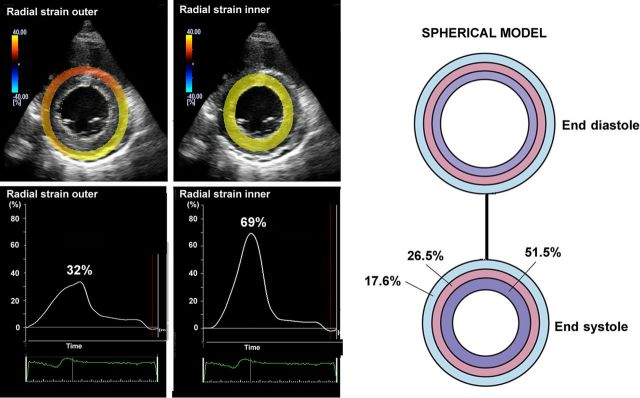

Most laboratories record LV strain in the long axis and use global longitudinal strain (GLS) calculated as the average from all segments, as a measure of global LV function. Figure 1 shows typical segmental strain traces in a normal heart. Images for GLS are made in standard apical two-, three-, and four-chamber views and aortic valve closure (AVC) is used for timing of end-systole.10 When regional speckle tracking is suboptimal and recordings need to be rejected in more than two myocardial segments in a single view, the calculation of GLS should be avoided10 and other methods for measuring global LV function should be used. Normal GLS for most echocardiography systems is reported between 18 and 25% in healthy individuals, a variation, which in part may be explained by inter-software and inter-vendor variability. Technically, good recordings can be achieved along any axis, but interpretation of radial and circumferential strains are complicated by substantial transmural non-uniformity in the normal left ventricle. Figure 2 illustrates and explains this phenomenon which is entirely a geometric effect and does not imply differences in contractility between LV wall layers. For longitudinal strain, however, such geometrical effects are of less magnitude.

Figure 2.

Left panels: left ventricular short-axis view from a healthy individual showing higher radial strains in inner than outer layer. Right panel: Transmural difference in radial strain is a pure geometrical effect, since reduction in external diameter of a passive circular structure leads to more thickening of inner than outer layers. The figure simulates reduction of inner radius by 25% and the numbers indicate the resulting thickening in inner, mid and outer wall layers.11